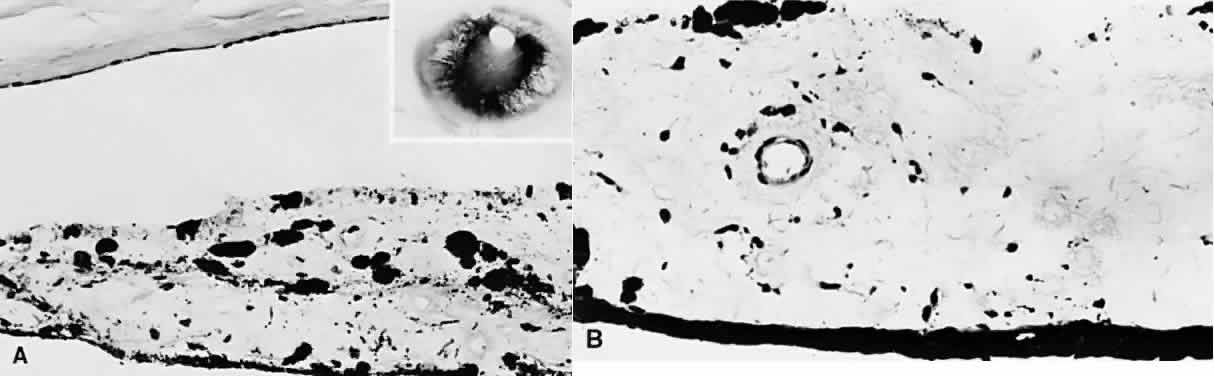

Prolonged elevation of IOP results in characteristic histopathologic changes in the eyes of children 10 years of age or younger. These effects are independent of the specific etiology of the IOP elevation. Ocular stretching, particularly at the corneoscleral limbal region, results in limbal ectasia and the clinical appearance of buphthalmos (Fig. 3). If the thinned and stretched limbus is also lined by uvea (e.g., with peripheral anterior synechiae), a limbal staphyloma is present. When this area extends posteriorly to involve the ciliary body region of sclera, it is called an intercalary staphyloma.

Fig. 3. Congenital glaucoma with enlargement, stretching, and thinning of the cornea and sclera, especially in the limbal region (limbal ectasia). Note the deep anterior chamber and the rupture in Descemet's membrane (arrow). Fibrosis of the iris root and trabecular meshwork is present. (Inset) Markedly enlarged corneas in a child with bilateral congenital glaucoma. (Main figure, H&E, × 8; inset, clinical)

The stretching of the entire anterior segment of the globe is also reflected in corneal enlargement. The 95% range of normal corneal diameters is as follows: age 1 month, 9.4 to 11 mm; 6 months, 10.5 to 11.7 mm; 12 months, 10.8 to 12 mm.40 A corneal diameter of 11 mm or less is found in only 24% of patients with primary congenital glaucoma younger than 3 months of age, and in only 9% of those older than 3 months of age so afflicted.41

Progressive corneal enlargement ruptures Descemet's membrane (Haab's striae). These breaks, which are usually horizontal in the central area and concentric toward the limbus, are generally in the lower half of the cornea and are usually associated with corneal edema (see Fig. 3). As in glaucoma in the adult, optic nerve cupping is a characteristic and diagnostic finding in congenital glaucoma. In congenital glaucoma, however, cupping is an early finding and is frequently reversible in its early stages.

Late manifestations of congenital glaucoma include fibrosis of the iris root and trabecular meshwork, disappearance of Schlemm's canal, and generalized atrophy of the ciliary body, choroid, and retina.